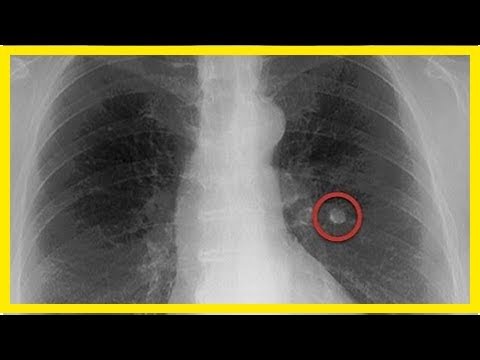

Definition von Lungenknoten Ein Lungenknoten ist definiert als ein Fleck auf der Lunge mit einem Durchmesser von 3 cm oder weniger. Bis heute sind die Möglichkeiten der Früherkennung begrenzt die bisher geprüften Untersuchungen sind belastend und nicht ohne Risiko. Wie auch bei der COPD ist der größte Risikofaktor für die Entwicklung eines Bronchialkarzinoms das Rauchen.

Lungenkrebs Farbig X Ray Zeigt Krebs In Theleft Lunge Eines 55 Jahre Alten Patienten Stockfotografie Alamy